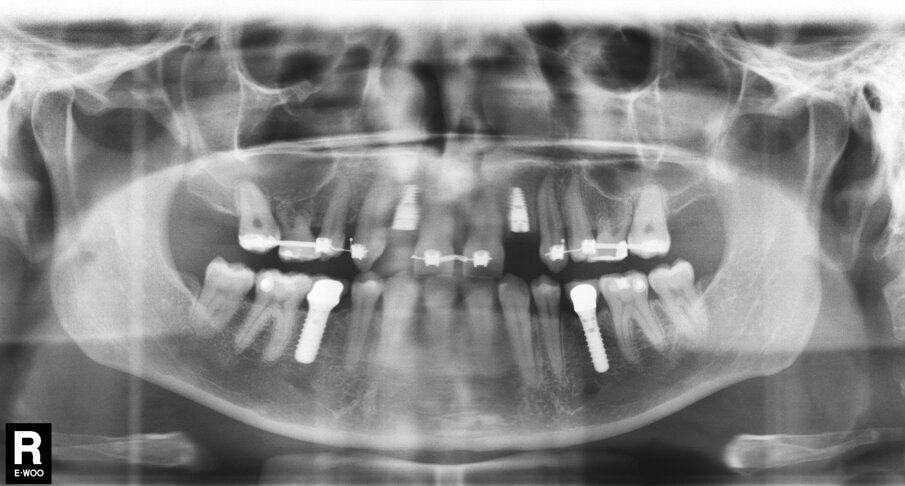

In deze casus is indertijd voor tissue level-implantaten gekozen en na ongeveer achttien jaar in functie is de esthetiek, mede door de vorm van de cuspidaten en het zichtbaar worden van de implantaten, discutabel te noemen (afbeelding 1 en 2).

In samenspraak met de patiënte en in goed overleg met de behandelend orthodontist werd besloten de implantaten op de posities 13 en 23 te verwijderen, de cuspidaten naar distaal te verplaatsen en de angulatie van de elementen te corrigeren, zodat het plaatsen van twee implantaten op de posities van de laterale incisieven goed mogelijk zou worden (afbeelding 5 en 6).